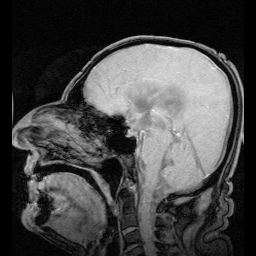

استسقاء المخ كما يظهر في الأشعة المقطعية على المخ. المناطق السوداء في منتصف المخ هي تضخم غير طبيعي ومملوء بالسوائل. | |

يعتمد التشخيص على التاريخ المرضي والفحص السريري، ومعرفة الحالة المصاحبة، بالإضافة إلى بعض الفحوصات الإشعاعية مثل :

- الأشعة المقطعية : وتعطي صور واضحة عن الحالة ومكان الانسداد.

- الأشعة فوق الصوتية : وتعطي صورة عن تطور حجم البطين وتستخدم في المتابعة.